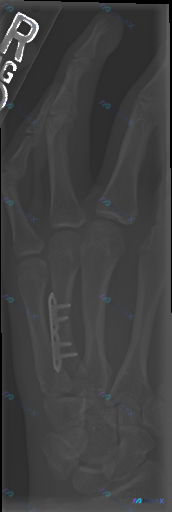

这张右手斜位X线片显示“愈合良好”,但有没有可能漏了什么?

整理到一张右手斜位X线片的读片资料,先给大家看客观影像表现:

- 第4掌骨干有金属接骨板+螺钉固定,位置看起来还行

- 原骨折线已经模糊/消失,骨皮质连续

- 其他掌指骨、关节间隙、软组织看起来都没明显异常

影像报告首先考虑「第4掌骨骨折术后愈合状态」,但这份资料后面附的临床思维复盘提了几个挺有警示性的点——比如「无软组织肿胀≠无感染」「骨折线模糊也可能是骨溶解」。